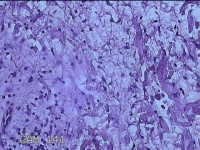

左侧会阴部结节

性别

女

年龄

43岁

临床诊断

皮肤良性肿瘤

一般病史

发现右侧会阴部结节3年余。

标本名称

大体所见

灰白粉红色带皮肤结节0.8x0.7x0.3cm一个,表面光滑,切开结节呈实性,切面灰白粉红色,质韧。

图4